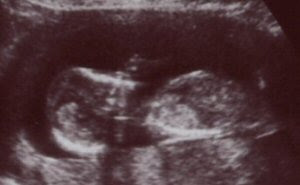

Los días pasan y ya son más de 13 semanas las que tiene este pequeñín, que vive en el vientre de su madre esperando que llegue el momento de ver la luz del mundo exterior. Ya tiene sus bracitos, sus manitas, sus piernecitas, sus piececitos, un diminuto estomaguito, un palpitante corazón... Poco a poco va formándose y va ganando tamaño. Ahora mide poco más de siete centímetros y sus padres lo contemplamos emocionados, ilusionados.

De costado, llevándose la manita a la cara

Desde su cálido hogar, que le nutre y le permite desarrollarse sano y fuerte, nos observa desafiante, mostrando su semblante como si preguntara: "¿quién anda ahí?"

Aquí estoy yo